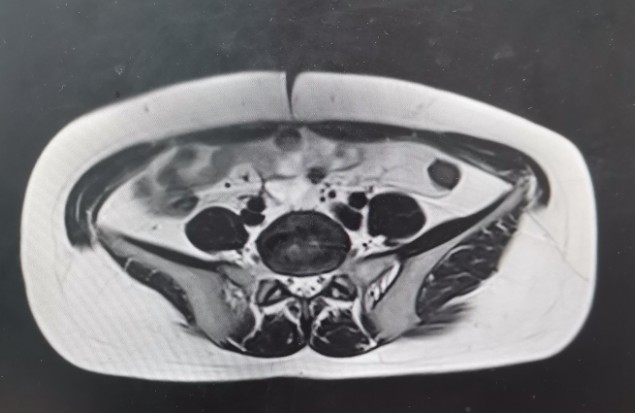

•全腹核磁:子宫术后改变,脂肪肝,双肾囊肿,盆腔少量积液。

轴位T1

轴位T2

矢状位T1

矢状位T2